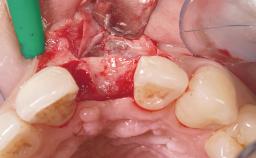

Late Flapless Placement of an Implant in a Maxillary Left Central Incisor Site

A 39-year-old male patient presented with a chief complaint of discomfort and gingival discoloration around his maxillary left central incisor. He was in good general health and was a non-smoker. His past dental history was significant because of the traumatic fracture of tooth 21 in a sporting accident at age 13. Initial dental treatment included endodontic therapy and a full-coverage restoration. The patient became symptomatic 5 years later, when structural failure of the tooth resulted in the dislodgment of the crown. Endodontic retreatment, apical surgery, and post-and-core restoration were performed.

Bone Volume Deficient horizontally, requiring prior grafting

Bone Augmentation Horizontal|Staged